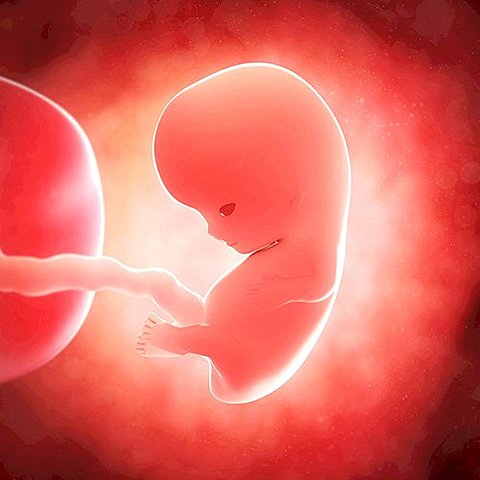

• Novena semana

Novena semana

En la semana 9 de embarazo, el embrión mide 13-17 milímetros, aproximadamente, desde la coronilla hasta las nalgas.

Sus huesos empezarán a desarrollarse –y seguirán creciendo hasta la adolescencia, las vértebras y costillas ya están en su sitio y el esqueleto del bebé se calcificará y endurecerá gradualmente.

• semana 10 y 11

semana 10 y 11

Estas dos semans se cenran mas en el aparato digestivo, los intestinos se desplazan hacia el abdomen y las lesiones un movimiento rotatorio que los coloca en su posición anatómica correcta. Los dedos de sus manos y de sus pies se han definido. Durante estas semanas, se inicia el desarrollo de las uñas. Esta etapa se caracteriza ya que el hígado es el principal organismo productor de sangre.